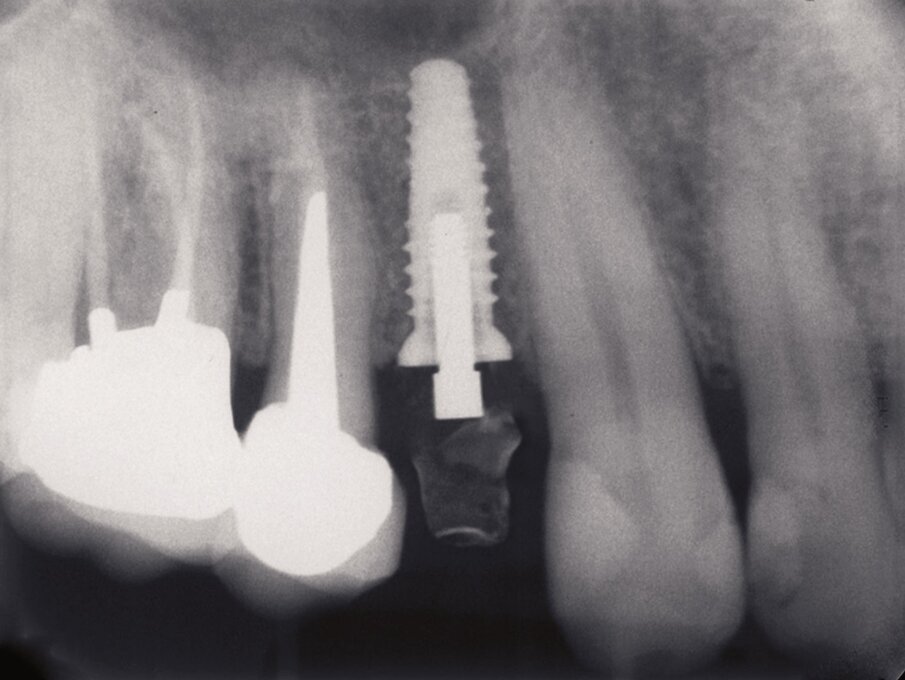

Fig. 2a_Fase protesica provvisoria. Rx endorale di controllo in cui si nota il perfetto posizionamento implantare.